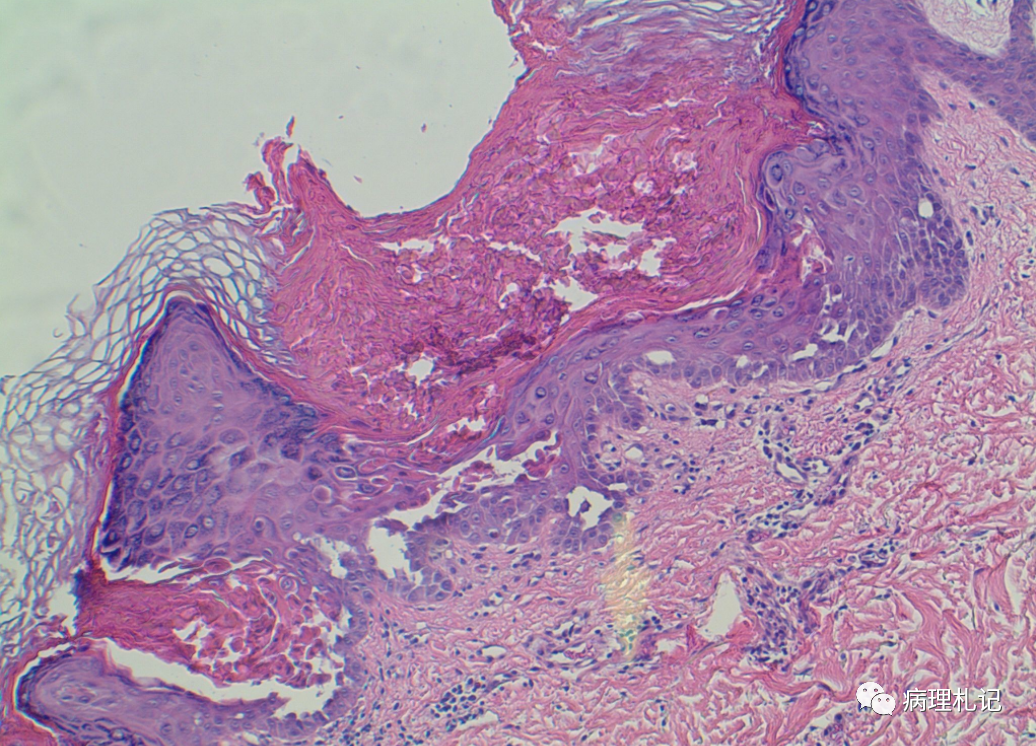

弥漫性神经纤维瘤中惊叹wagnermeissner小体